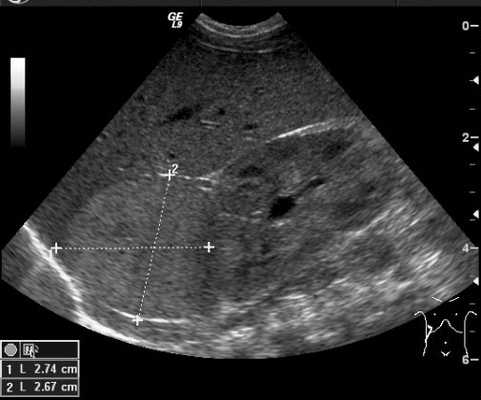

Результаты исследования: размеры плода пропорциональные, соответствуют менструальному сроку беременности. При эхокардиографии особенностей строения сердца у плода не выявлено. При оценке органов мочевыделительной системы обнаружено следующее: правая почка плода нормальных размеров и структуры. Левая почка увеличена до размеров 53х38х46 мм при 95-м процентиле нормативных для срока значений 43х24х23 мм [4] (рис. 1). В структуре почки, преимущественно в верхнем и среднем сегментах, определяется округлое образование без четких контуров, средней эхогенности, приблизительные размеры его 50х35х35 мм. При цветовом допплеровском картировании в образовании визуализируется обширная сосудистая сеть. При допплерометрии индексы сосудистой резистентности (рис. 2) в разных участках образования варьируют в широких пределах (от 0,49 до 0,77).

Рис. 2. Режим цветового допплеровского картирования. Хорошо видны различия в характере васкуляризации нормальной почки и контрлатеральной пораженной почки.

В представленном клиническом наблюдении диагноз опухоли почки был поставлен нами практически сразу и не вызывал сомнения, поскольку стандартный протокол ультразвукового скринингового исследования во II и III триместрах беременности требует описания почек и мочевого пузыря. Почки оцениваются в поперечном и продольном сечениях с использованием при необходимости цветового допплеровского картирования (рис. 3, а, б). В данном случае почки плода располагались в типичном месте, но обращали на себя внимание значительная разница в размерах и необычная структура одной из почек (см. рис. 1). В 2D режиме границы опухоли четко не визуализировались, но при использовании технологии VCI (объемное контрастное изображение) можно было более точно определить ее контуры (рис. 4).

Рис. 3. Исследование почек.

а) Поперечное сканирование. Переднезадний размер почек обозначен стрелками.